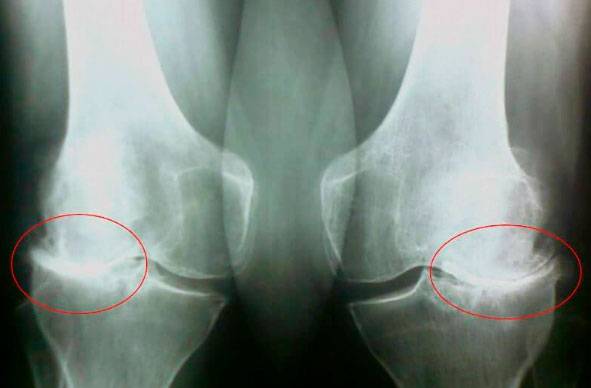

Бу суратларга қаранг, ўнг суратда бўғим оралиғи йўқ, суяклар бир-бирига ишқаланиб, қаттиқ оғриқ чақиради. Одам икки йилдаёқ ногиронга айланади.

С.М. Бубновский: Аввало бу жароҳатлар ва жиддий юкланишлар. Семизлик ҳам бўғимларга ёмон таъсир кўрсатади. Камҳаракат турмуш тарзи, стресслар, овқатда туз ва шакар кўплиги – буларнинг бари тоғай тўқимасини юмшатади, емиради ва нозиклаштиради. Ҳар бир ҳаракат сари тоғай едирилиб, деформацияланади, суяклар бир-бирига ишқаланиб, қаттиқ оғриқ чақиради..